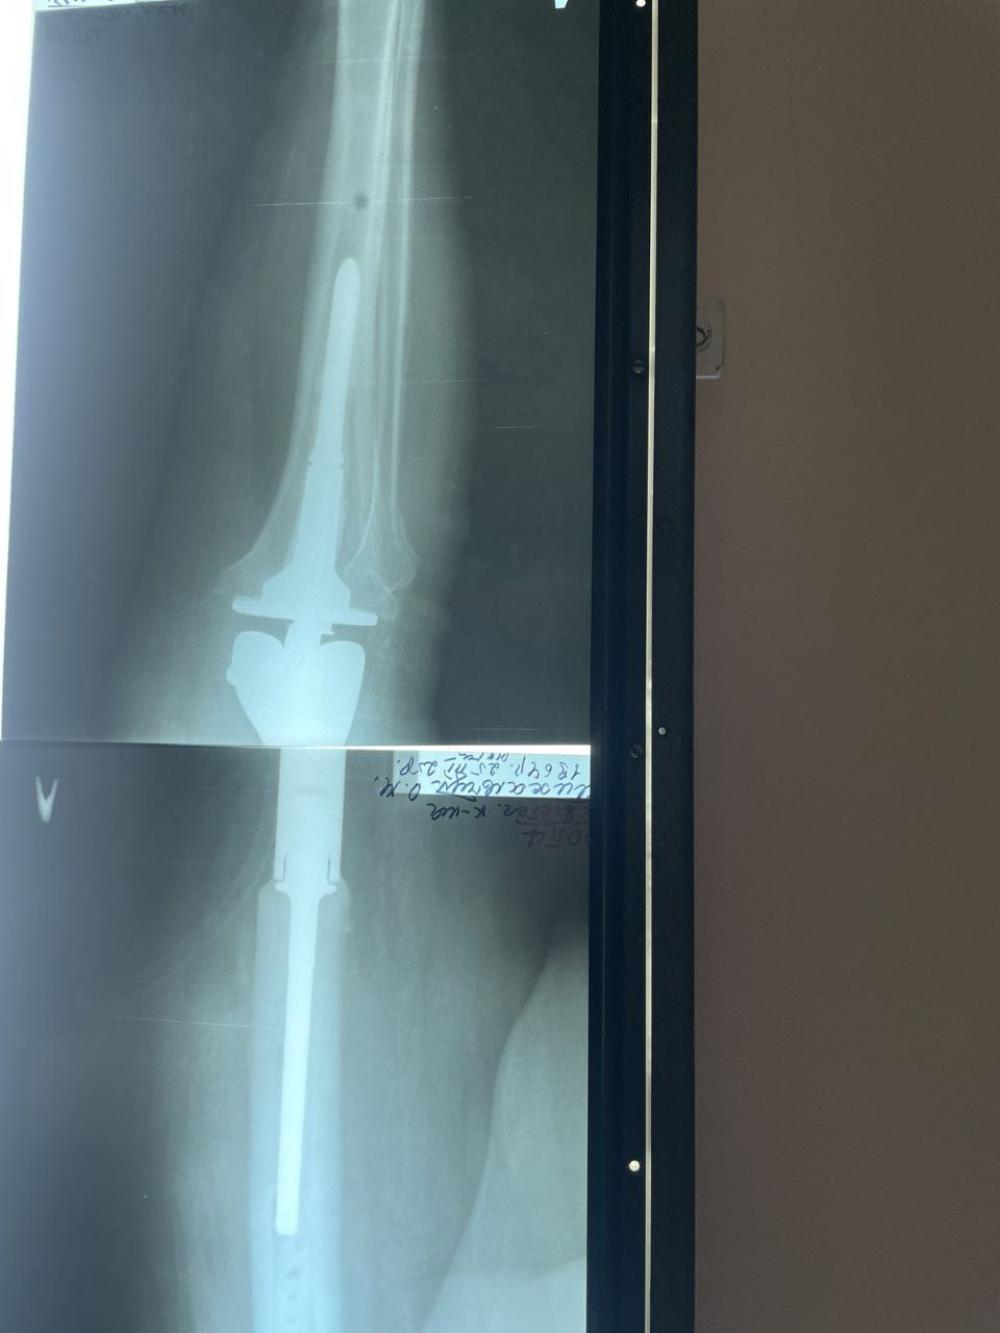

Унікальну операцію провели у Рівненському обласному протипухлинному центрі. Мова йде про резекцію стегнової кістки з видаленням метастатичної пухлини та мегатотальним ендопротезуванням.

Це перша подібна операція у Рівненській області, яка проведена онкологічному хворому, коли альтернативою ампутації кінцівки було протезування.

Операція проведена бригадою хірургів на чолі з професором Володимиром Проценком (Інститут травматології та ортопедії НАМН України) спільно з лікарями Рівненського обласного протипухлинного центру.